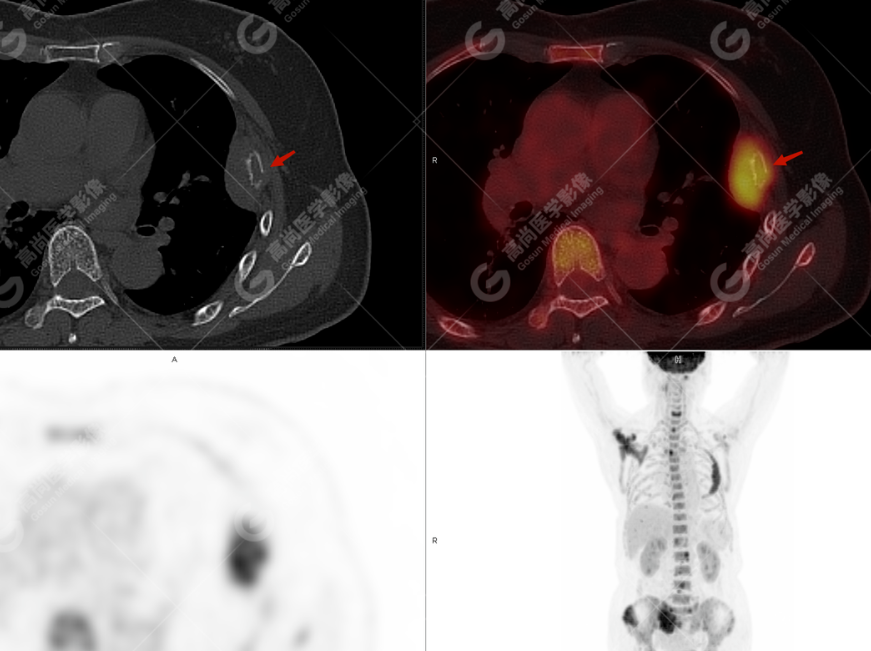

颅骨、寰椎前弓左侧份、第 6 颈椎、双侧肩胛骨(右侧为著)、左侧第 4 肋骨、第 1 胸椎、第 4 胸椎、第 2 腰椎及附件、第 4 腰椎及附件、骶骨、右侧髂骨、左侧坐骨结节、左侧股骨颈、双侧股骨小转子等均不同程度骨质吸收、破坏,其中右侧肩胛骨、左侧第 4 肋骨及骶骨右侧份软组织肿块影形成,上述病变均考虑恶性肿瘤(血液系统来源,多发骨髓瘤可能性大),建议右侧髂骨翼穿刺活检明确。

(4)PET-CT 影像表现:在溶骨性破坏区出现相重叠的 18F- FDG 高代谢区;通常呈弥漫性高代谢区。